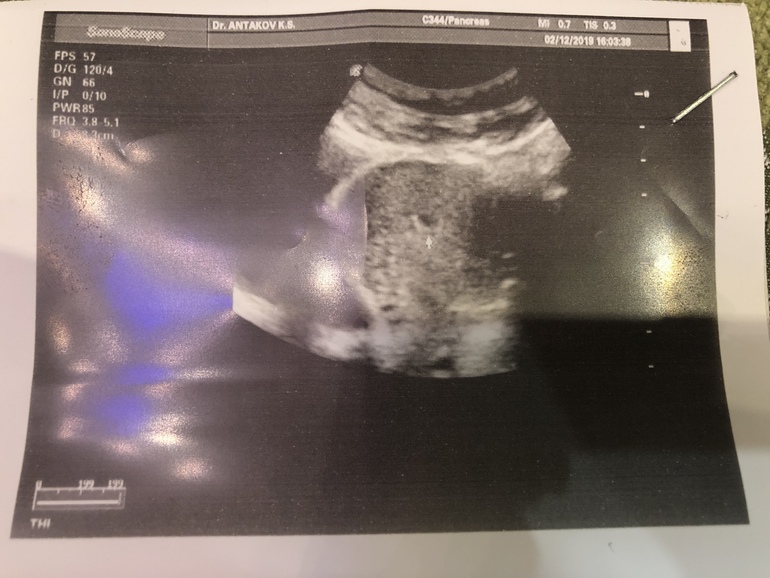

Узи было быстрое, врач мужчина, смотрел датчиком по животу, сказал, вот плодное яйцо , все хорошо 🤦🏻♀️😁 я даже не успела ничего сказать , пошла платно.

14.12.2019 . Я пошла на УЗИ , чтобы послушать сердечко маленького , когда услышала сердечко , улыбка на моем лице была до ушей , и я не могла остановиться улыбаться , не передать словами , что я испытала в эти секунды, мой первый малыш, первое сердечко, ...